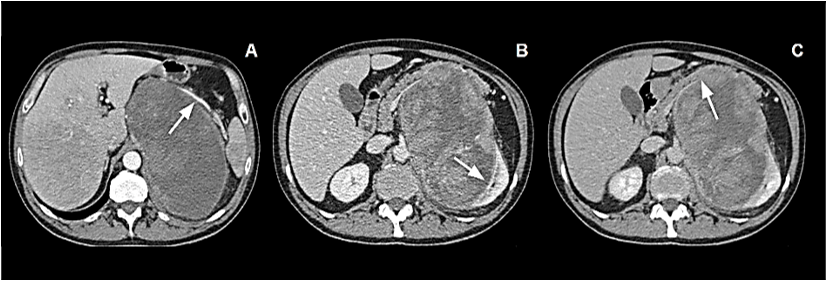

A consultant surgeon hypothesized origin of the mass from left kidney or left adrenal gland and addressed patient to further investigations. Head and chest contrast CT scan revealed normal findings. Abdominal CT scan showed a well-defined extensive mass, of regular contours and with heterogeneous signs, suggesting hemorrhagic and necrotic areas, arising from left adrenal lodge. It measured 18 x 11 x 10 cm in its greatest dimensions. The mass crossed the midline and displaced the spleen, the pancreas, and the left kidney. On arterial phase, splenic artery was grossly displaced and stretched upwards (Figure 1A). Venous and delayed phase confirmed dis-homogeneous aspect of the tumor and respectively clear evidence of displacement and absence of cleavage with the left kidney (Figure 1B) and strict adhesion with lower margin of pancreatic body and tail (Figure 1C). Neither infiltration of the IVC nor endovascular thrombotic figures could be demonstrated; no enlarged lymph nodes could be detected.

Figure 1: A) Arterial phase: Giant mass occupying left abdomen. Splenic artery appears stretched upward. B) Venous phase: Inhomogeneous mass displacing and probably infiltrating left kidney. C) Delayed phase: Absence of clear cleavage with pancreatic body and tail.